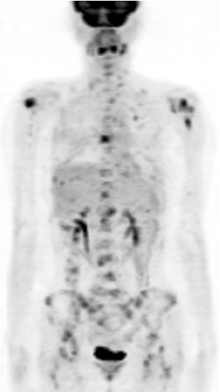

张国淳:该患者在完成了6个周期的XT方案之后又进行了一次PET疗效评价, 结果显示:与2009-08-25本院PET影像比较, 未见明确新发病灶, 原肝脏左叶病灶及乳腺病灶消失, 见图4。而CA15-3及CEA均降低至正常范围内。那么此时右乳局部复发灶是否应该进一步处理?

张国淳:该患者在术后再予2周期XT方案化疗后予内分泌维持治疗, 方案为戈舍瑞林卵巢去势加阿那曲唑, 并予氯膦酸二钠抗骨转移治疗。患者在2010年4月行PET复查时发现左上肺、肝左叶及全身多处骨髓局灶性葡萄糖代谢异常增高灶, 与前次PET影像比较, 以上均为新发病灶(见图5)。患者一线治疗的无进展生存期为8个月。患者此时拒绝化疗。改用依西美坦内分泌治疗。2010年8月复查胸腹部CT提示双肺多发性转移癌, 右侧胸腔积液, 纵隔、肺门淋巴结肿大, 肝多发性转移瘤, 多发性骨转移瘤, 提示疾病再次进展, 见图6和图7。患者此时同意任何形式的治疗, 包括化疗。那么此时应该如何选择治疗方案?